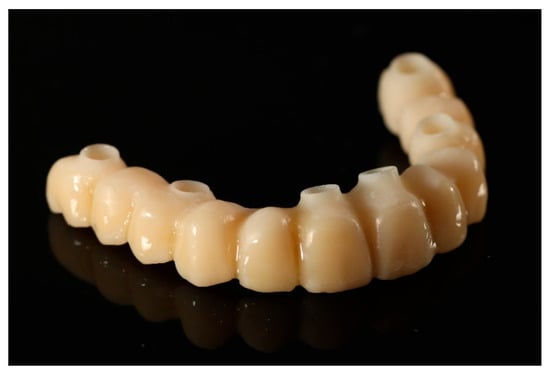

Based on the merged datasets (biocopy + SmartFlags® scan), the provisional screw-retained, implant-supported full-arch prosthesis was designed in Exocadsoftware (Exocad GmbH, Darmstadt, Germany) and subsequently fabricated using OnX Tough 2 resin (SprintRay Inc., Los Angeles, CA, USA) by means of 3D printing. The intaglio (tissue-facing) surface was polished [18], while the labial surface was characterised and glazed to improve aesthetics (Optiglaze Clear, GC International AG, Luzern, Switzerland). As demonstrated in the accompanying clinical photographs, minor superficial cracks in the glaze layer are visible on the external surface of the prosthesis (Figure 8).

Figure 8. A digitally planned, 3D-printed full-arch provisional restoration ready for assembly.